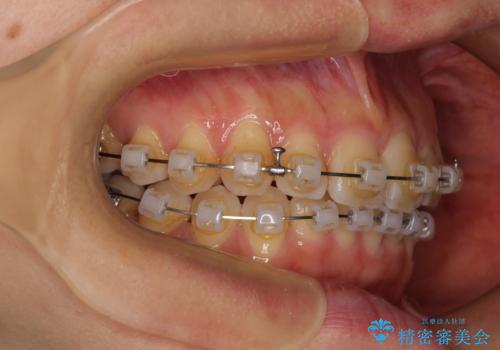

- クリアブラケット

- 上下前歯のデコボコを気にして来院された患者様です。

叢生は軽度で、ワイヤー矯正でもマウスピース矯正でも対応可能な歯列でした。

僅か1年間できれいに歯列を整えることができ、患者様には大変満足していただきました。